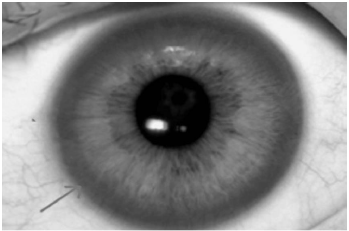

Ao exame: Lúcida, orientada, porém com disartria e disfonia, eupneica em ar ambiente, anictérica, afebril. FC: 64 bpm, PA: 110x60 mmHg, SatO2: 97%. Presença de marcha atáxica, tremor de repouso, dismetria, e um halo marrom-dourado na periferia da córnea e contornando a íris (figura abaixo – seta) em ambos os olhos. MVUA sem ruídos adventícios, ritmo cardíaco regular em 2T sem sopros ou turgência jugular. Fígado palpável a 8 cm do rebordo costal (hepatimetria 14 cm). MMII sem edema.